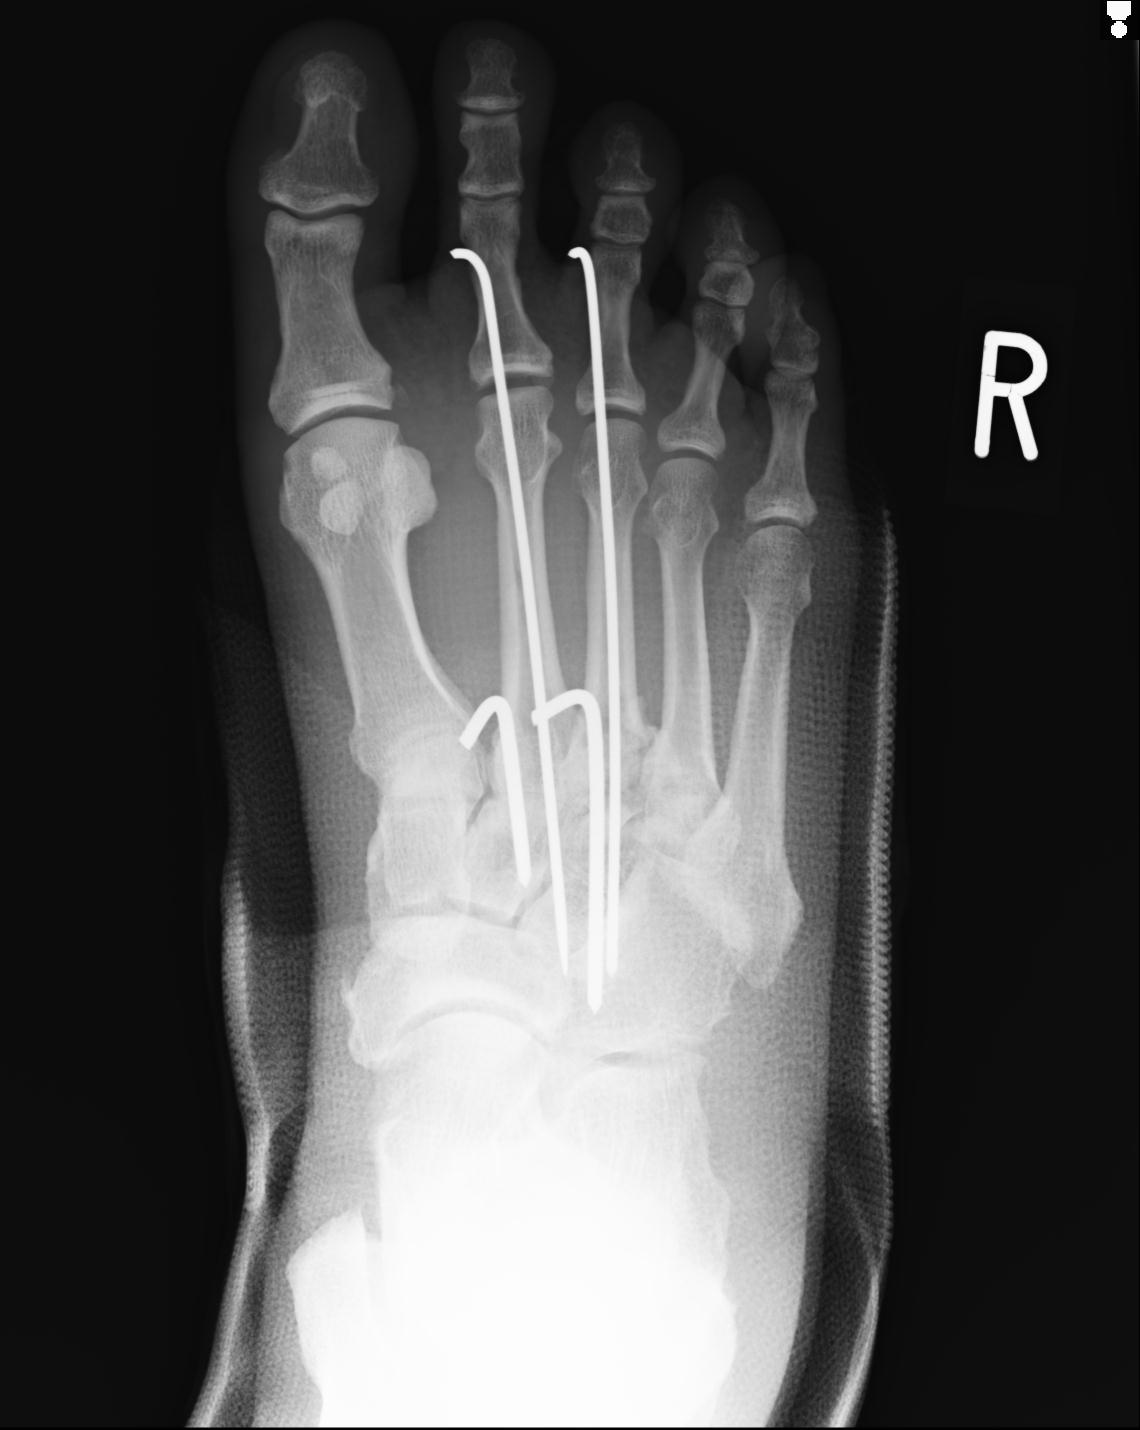

103177 3/11 右足 2R 3/16 右足 2R リスフラン脱臼 55歳男性